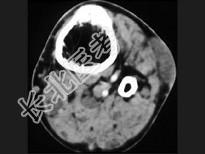

- 单项选择题男,35岁, 皮肤可见咖啡色素斑,关节疼痛, 结合图像,最可能的诊断是 ( )

A、骨肉瘤

B、骨转移瘤

C、神经纤维瘤

D、骨软骨瘤

E、纤维肉瘤